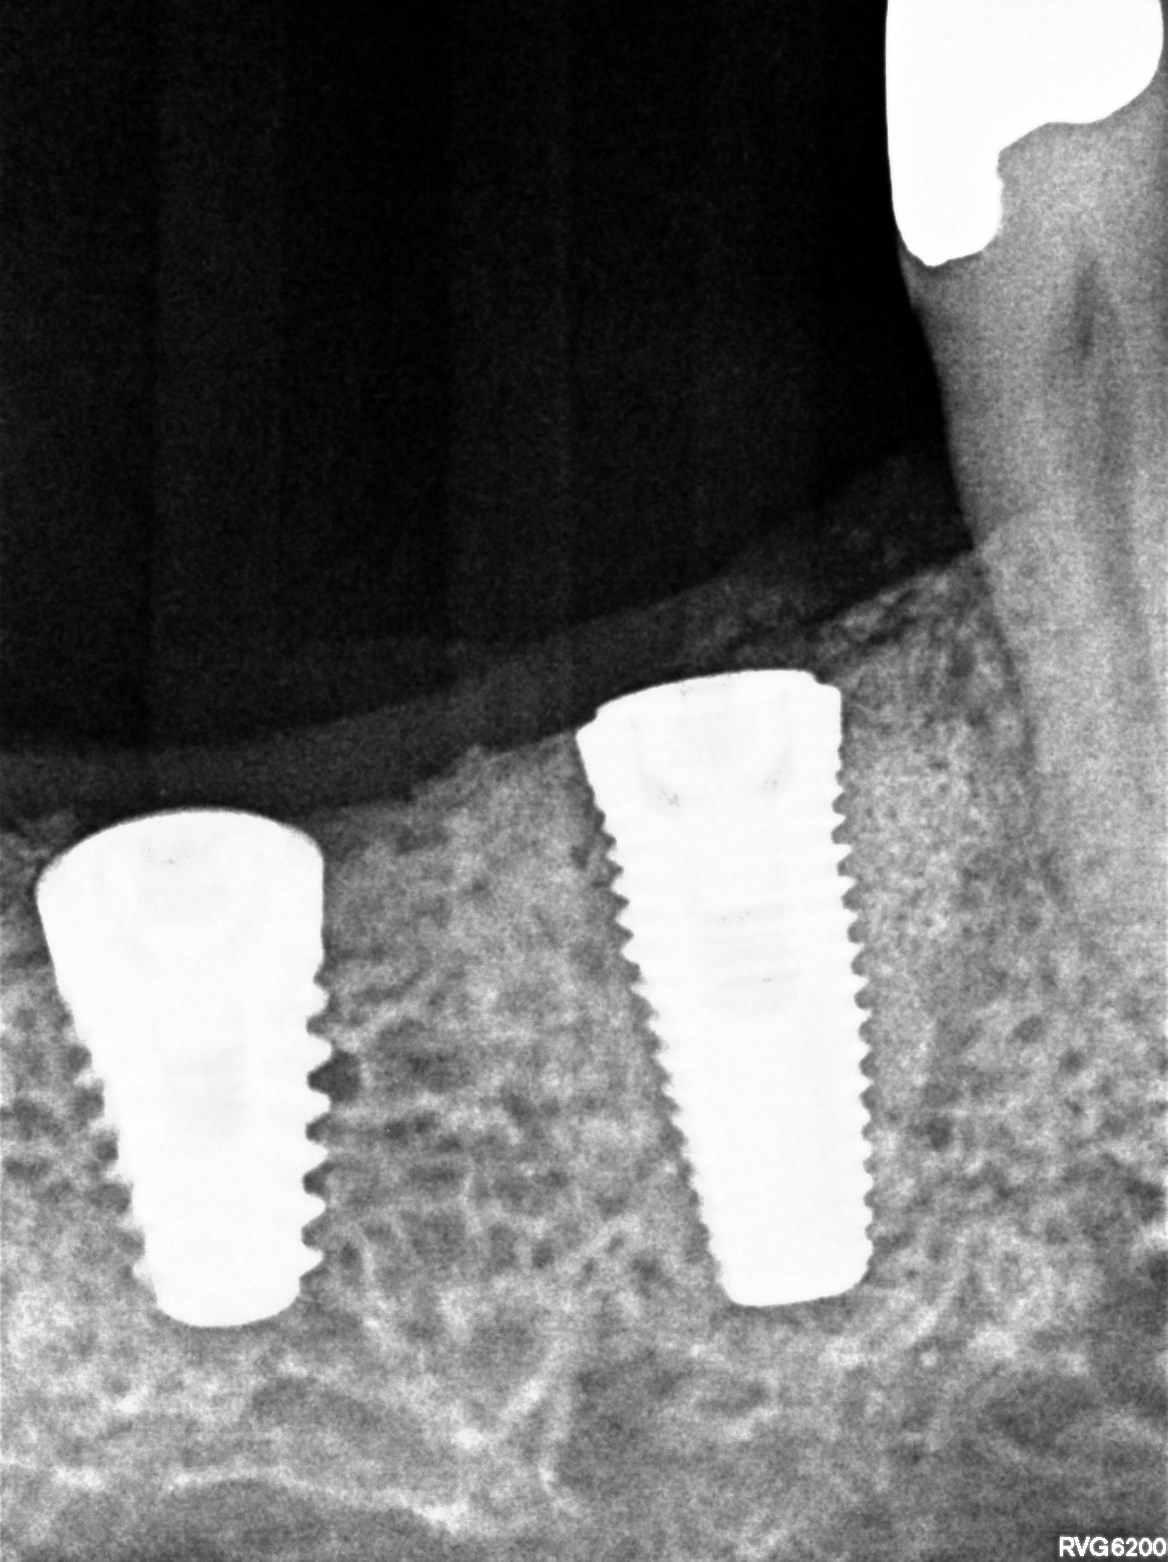

Il tunnel implantare è molto vascolarizzato. Viene inserito un impianto Neoss Tapered 4,5x11 mm, bone level, con torque di inserimento di 60 Ncm e ISQ 75 (Figure 20-22).

Dopo ulteriori quattro mesi si può procedere con l’ultima fase chirurgica di scopertura delle due fixture e di inserimento di abutment definitivi personalizzati.

Dopo l’apertura del lembo di accesso si evidenzia tessuto osseo corticalizzato anche nella zona vestibolare e crestale di 4.5. La visione occlusale consente di apprezzare la ricrescita ossea coronale alla vite tappo della fixture in 4.5 e del tessuto osseo vestibolare rispetto al bone housing. La misurazione ISQ di 4.5 restituisce l’alto valore di 86 (Figure 23-24).